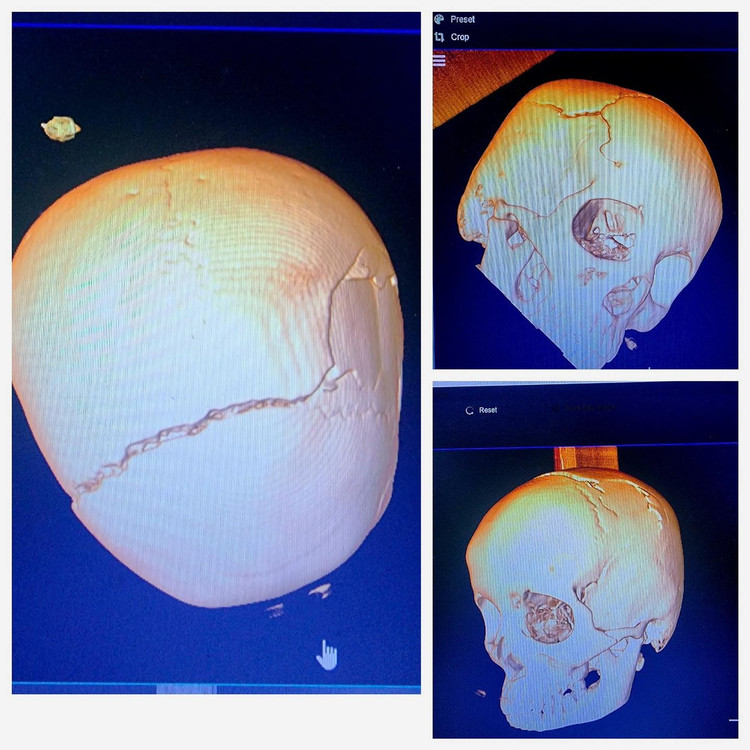

2-lan-mo-nao-4.jpg

Hình ảnh sọ vỡ trên phim chụp - Ảnh BVCC